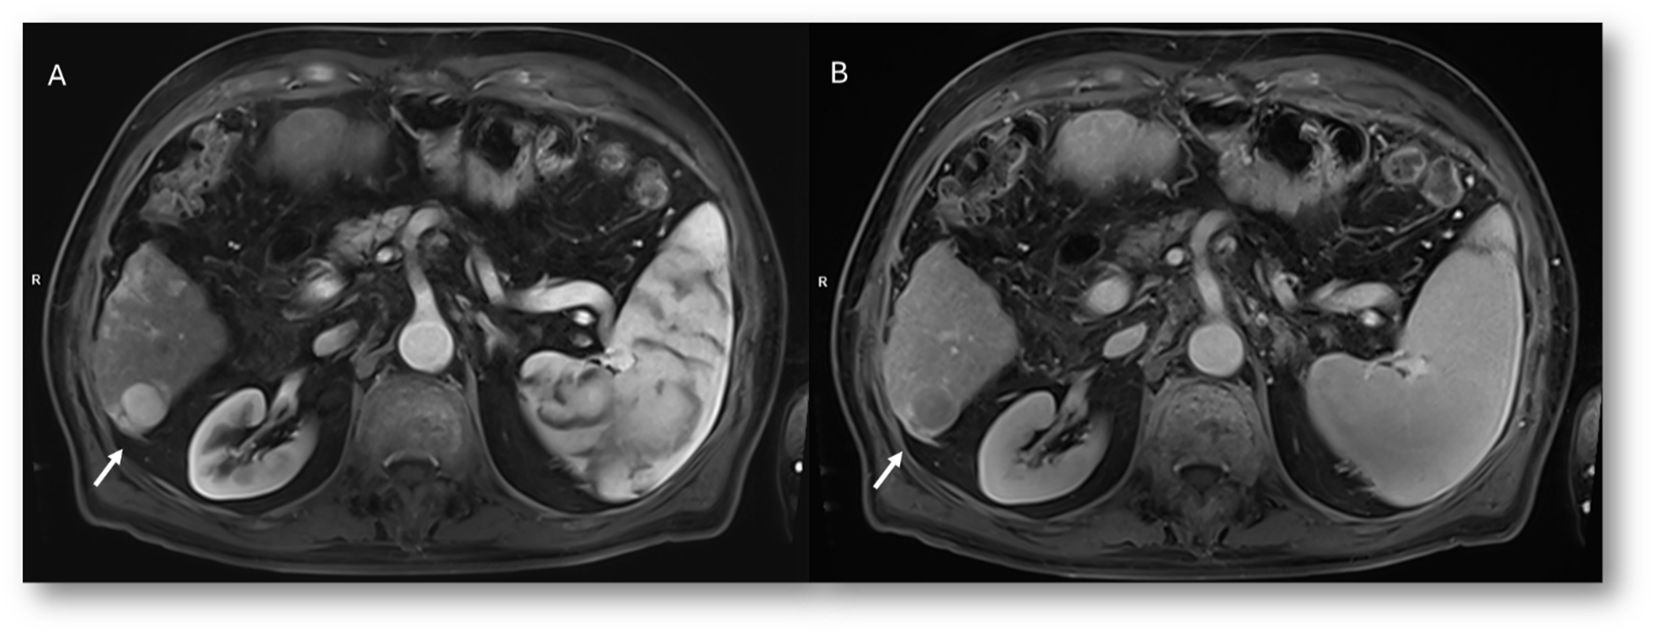

Figure 6. MRI assessment of colorectal liver metastases with Gd-EOB-DTPA contrast during multi-arterial phase: motion artifacts on all phases with low image quality. (A–C) Sequence acquired on 3T VIDA System (Siemens, Germany) with deep learning AI technology.